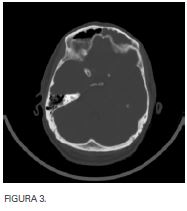

Se decide realizar cirugía urgente con unciformectomía, meatotomía media, etmoidectomía anterior, acceso a ambos recesos frontales con cultivo de contenido purulento de seno frontal derecho por vía endoscópica; por parte de neurocirugía actitud expectante. Tras mejoría clínica inicial y a pesar de no llevar taponamiento nasal, a las 32 horas presenta aumento de la cefalea frontal, así como occipital por lo que se realiza estudio radiológico urgente (figuras 3, 4 y 5). En el mismo se demuestra correcta aireación de seno frontal derecho así como progresión de empiema epidural con  componente subdural hacia convexidad derecha, desplazamiento de la línea media, paquimeningitis y cerebritis adyacentes. Pese a la gravedad de las imágenes el paciente no presenta focalidad neurológica y tiene una puntuación de 15 en la escala de coma de Glasgow.

En este momento se realiza craneotomía derecha para evacuación del contenido purulento intracraneal. También se realiza nueva exploración endoscópica, no apreciando solución de continuidad

entre el espacio epidural y el seno frontal derechos.

Tres semanas después con tratamiento antibiótico dirigido por antibiograma el paciente, asintomático, es dado de alta, habiendo desaparecido la colección intracraneal y apreciando únicamente engrosamiento de la mucosa de revestimiento del seno frontal derecho en la Resonancia Magnética Nuclear.